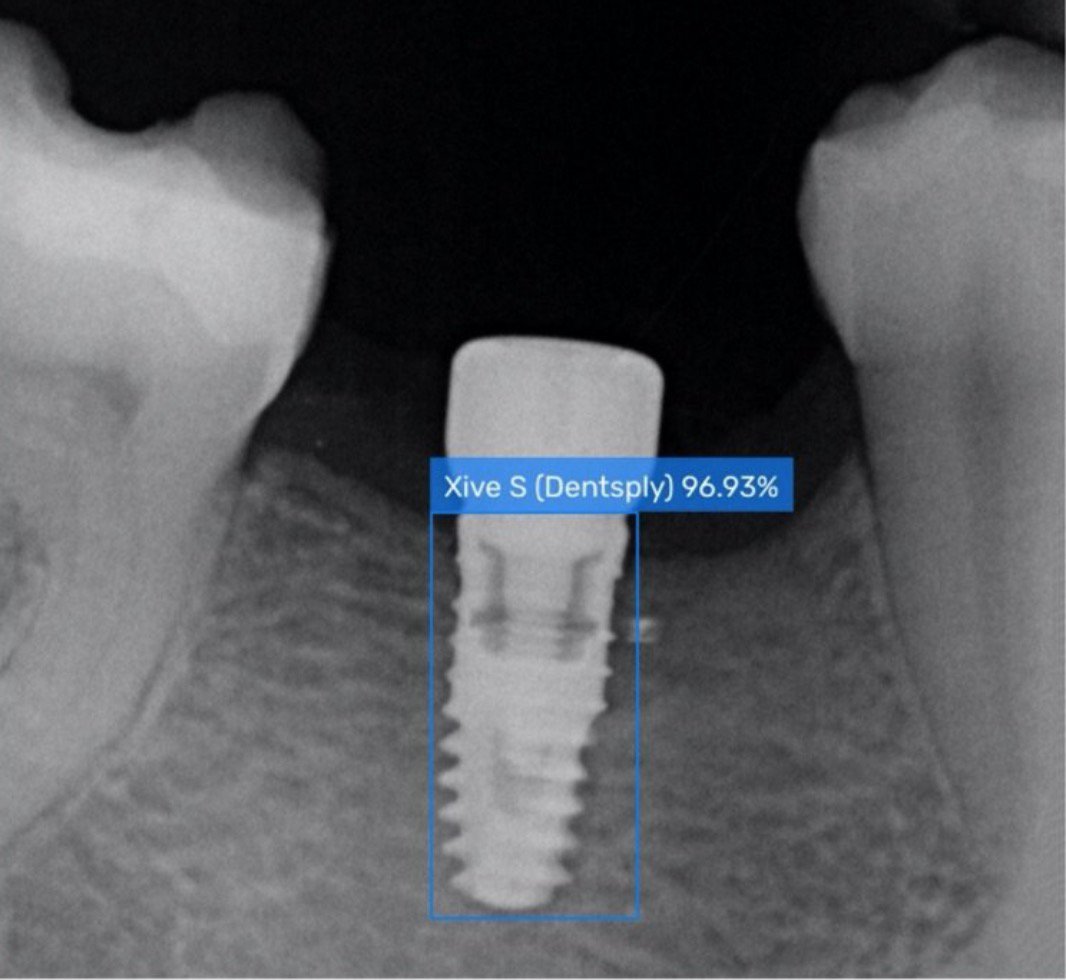

From www.spotimplant.com

Dental Implant Identification Service AIbased Spotimplant How To Identify An Implant learn to characterize and identify dental implants from radiographs using a free online database and consultation service. Spotimplant.com also offers an artificial. spotimplant is the most comprehensive dental implant database with thousands of brands, models and catalogs. learn how to identify unknown dental implants using radiographs, online databases, and implant identification services. Most people look at things. How To Identify An Implant.

How to Identify a Dental Implant How To Identify An Implant Spotimplant.com also offers an artificial. learn how to identify unknown dental implants using radiographs, online databases, and implant identification services. learn to characterize and identify dental implants from radiographs using a free online database and consultation service. Most people look at things differently, so it is important to find a common denominator and build on that. when. How To Identify An Implant.